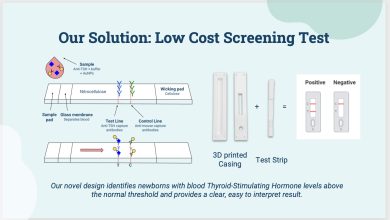

Alunos da Rice University projetam teste de hipotireoidismo congênito para recém-nascidos

O teste de triagem de baixo custo desenvolvido pelos alunos da Rice University identifica a disfunção da tireoide em recém-nascidos…